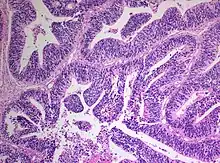

Medulloepithelioma, on the other hand, are tumors involving the constant cell division on the epithelium tissue where bundle of neuron endings are located.[1] Such tissue will differentiate into a similar form as the embryonic neural tube, also known as the starting structure of the central nervous system.[1][2][3] Medulloepitheliomas also present a pattern known as rosettes, characterized by the arrangement of a bundle of cells into circular shapes and around a center or a neuropil.[1] Ependymoblastoma also present rosettes as well as a higher density of cells.[1][3] It involves the process of differentiation into ependymal cells.[2][3]